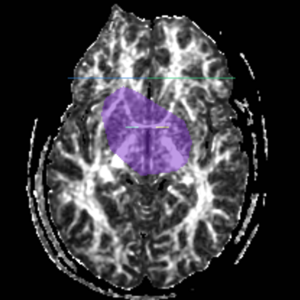

ROI 1) A coronal plane in the most anterior point of the corpus callosum was selected using the mid-saggital plane (Fig.18), and the left and right ROI1s were drawn on the superior side of the corpus callosum (Fig.15)

ROI 2) & ROI 3) The first coronal slice where the left and right corpus connect was selected: the left and right ROI2s were drawn on the superior side of the corpus and the left and right ROI3s were drawn on the inferior side of the corpus (Fig. 16 & 18)

ROI 4) The first coronal slice showing where the middle cerebellar peduncle was slected, and the left and right ROI4s were drawn(Fig. 17 & 19)

Figure 15. Coronal View of Cingulum Bundle ROI 1, Left and Right

Figure 16. Coronal View of Cingulum Bundle ROI's 2 & 3, left and right

Figure 17. Coronal View of Cingulum Bundle ROI 4, left and right

Figure 18. Cingulum Bundle ROI's 1, 2, and 3

Figure 19. Cingulum Bundle ROI 4

The color coding of the resulting ROIs is as follows:

ROI 1: Left(7) - Right(8)

ROI 2: Left(9) - Right(16)

ROI 3: Left(11) - Right(12)

ROI 4: Left(13) - Right(14)